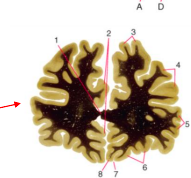

Huntington’s Disease

Loss of volume of Caudate Nucleo, enlargement of frontal horns

Enlargement of subarachnoid space, frontal convexity, interhemispheric scissure, sylvian region, and choroid fissures